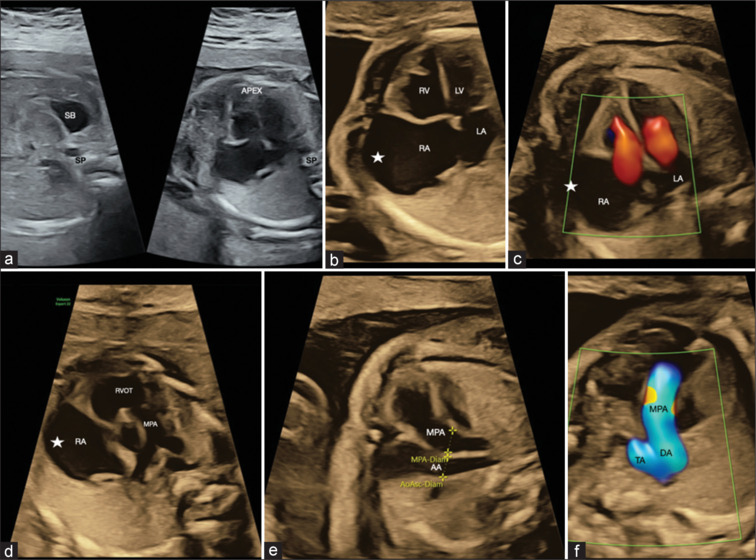

右心房动脉瘤(RAA)是一种罕见的先天性心脏畸形,可起源于心房或附件的游离壁。我们报告一个使用三维/四维时空图像相关胎儿超声心动图及其产后随访的产前诊断RAA的病例。

Right atrial aneurysm (RAA) is a rare congenital heart malformation that can originate from the free wall of the atrium or the appendage. We report a case of prenatally diagnosed RAA imaged using three-dimensional/four-dimensional spatiotemporal image correlation fetal echocardiography and its postnatal follow-up.